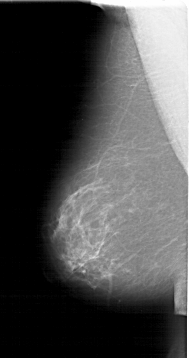

A_1170_1.LEFT_MLO

LEFT_MLO LINES 6436 PIXELS_PER_LINE 3391 BITS_PER_PIXEL 12 RESOLUTION 43.5 NON_OVERLAY